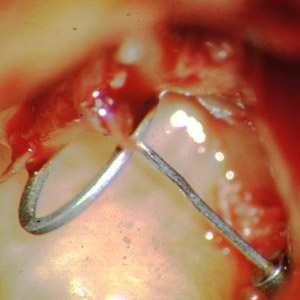

Tympanoplastik Typ 3b mit einer Titan-Total-Prothese wird die Verbindung zwischen Titanprothesen im Größenvergleich mit einem Streichholz.